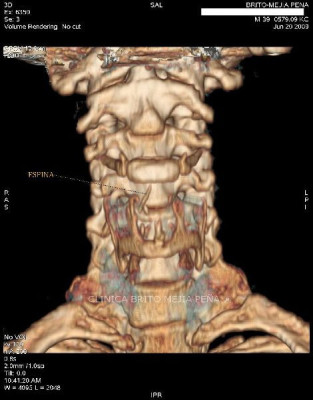

Espina en espacio retrofaríngeo